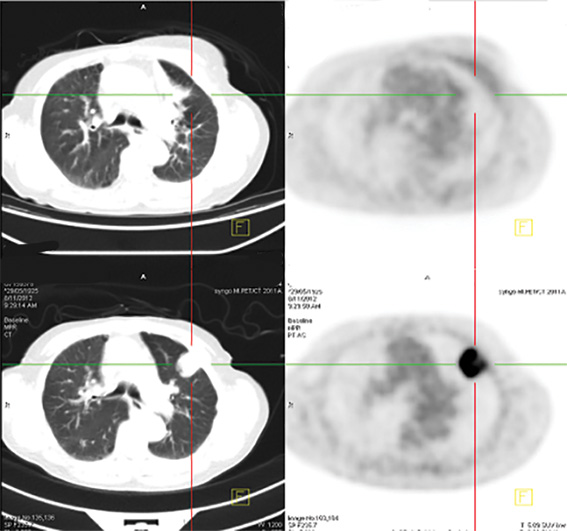

Stereotactic radiation treatment uses advanced imaging technology to deliver a high dose of radiation, very accurately and precisely to a tumour, sparing the surrounding sensitive organ.

“Stereotactic provides six times the strength of a conventional radiation dose, and is suitable for treating tumours less than five centimetre in diameter — generally early-stage cancers.